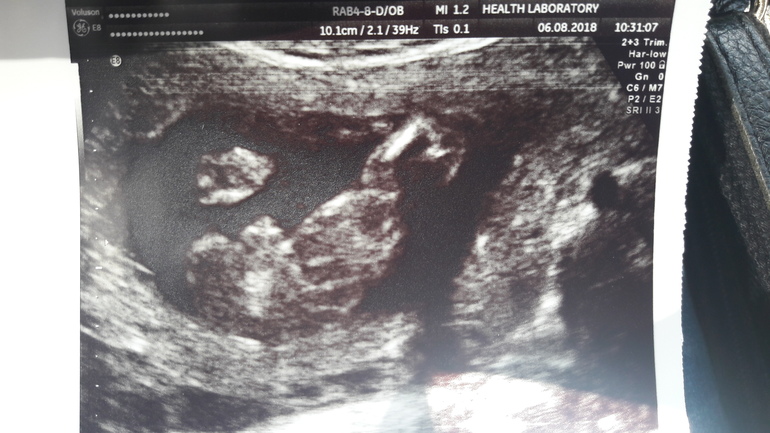

Пол малыша 18-19 недель

УЗИ, КТГ, доплерНу что,мамочки мальчиков!Жду ваших мнений как опытных)))Скоро с мужем годовщина,пошла все таки узнать пол и сделать подарок.Врач уверенно заявил-мальчик!Правда моя тихоня очень долго не показывался,прятал писюльку.Это ведь сын?Не могу поверить.....Неужели действительно обещанная 2 раза девочка превратилась в мальчика.....

А ее на фото нет,фото снизу,видно справа ножку полностью,слева не полностью,в центре-оно самое))))

Я у узиста спросила,не могут ли быть это половые губки и клитор,он сказал,что на этом сроке у девочек должен быть треугольник и губки восьмеркой(если честно,мне это описание с трудом в воображении представляется),а тут говорит мальчик.Муж очень сына хочет,мечтает многому его научить,надеюсь не отвалится))))))Просто по фото в интернете на фото мальчиков явные мужские причендалы,а мне кажется на моем фото очень миниатюрно,хотя может и ракурс такой.Радуют такие комментарии, как ваши,что фото похожи,а то прям не верится)))

Я вижу мужские причиндалы))

Нууу тут без сомнений сынок)))) вон все прелести, любуйся мама, называется)))